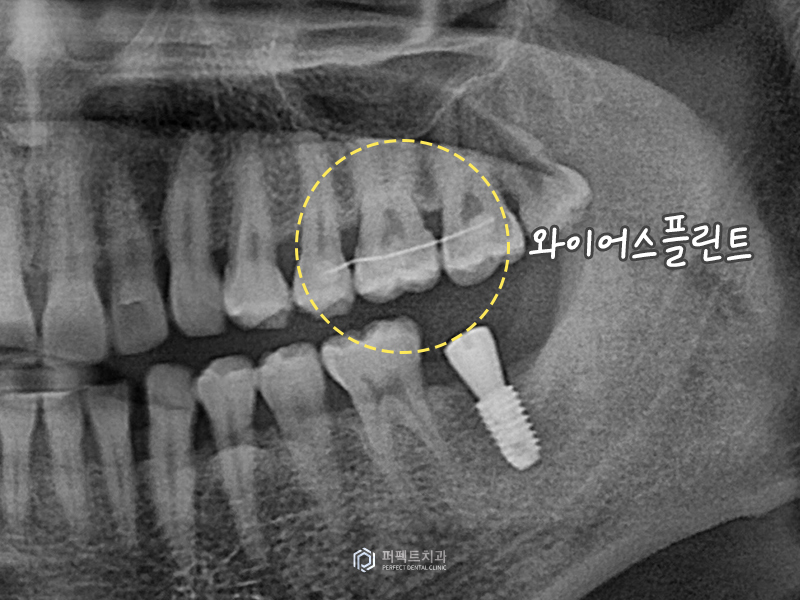

그렇기 때문에 환자 분들에게 이러한 내용을 우선적으로 설명을 드리고 본을 떠서 위 치아에 '와이어 스플린트'라고 하는 철사를 붙여 놓게 됩니다. 이렇게 하면 치아가 내려오지 않고 아래 임플란트가 완성되면 그 때 제거를 하면 됩니다.

사진을 보시면 위 치아에 철사가 붙여져 있는 것을 확인하실 수 있고 임플란트가 식립된 것을 확인하실 수 있습니다. 실제로 이 수술을 하는데 3분 정도 소요가 되었지만, 시간에 얽매이지 않고 정확도 위주로 진행을 하였습니다.

위 환자분의 경우 플랩 리스 수술(Flapless Surgery)로 실로 꼬매지 않는 방법으로 식립을 하였고, 깊이와 위치 모두 잘 식립이 되었습니다.